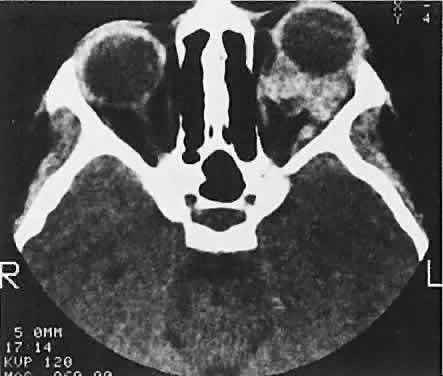

CT discloses a single or multilobulated mass, which represents only the blood cyst portion of the tumor (Fig. 14). Individual lobules may have different radiodensities depending on the presence of clots or liquefied blood within each cyst (Fig. 15). A generalized increase in orbital dimensions suggests a long-standing, probably congenital process. Echography may help differentiate the cystic components of lymphangioma from cellular rhabdomyosarcoma. Echography shows the blood cysts to be acoustically inactive spaces, with extremely low internal reflectivity (Fig. 16). Clots within the cysts can increase internal heterogeneity, however. MRI has virtually eliminated the need for diagnostic biopsy in this condition, because of its ability to show differing magnetic properties of suspended, degrading blood products (Fig. 17).

Fig. 14. CT appearance of hemorrhagic cysts in two different cases. A. A single intraconal cyst compressing the optic nerve. B. Multilobulated contiguous cysts. Intervening, nonexpanded segments are microscopic and not detectable with imaging studies.

Fig. 15. Lymphangioma with heterogeneous radiodensities. Clots were found in the denser anterior blood cysts, whereas the most posterior cyst had liquid contents.